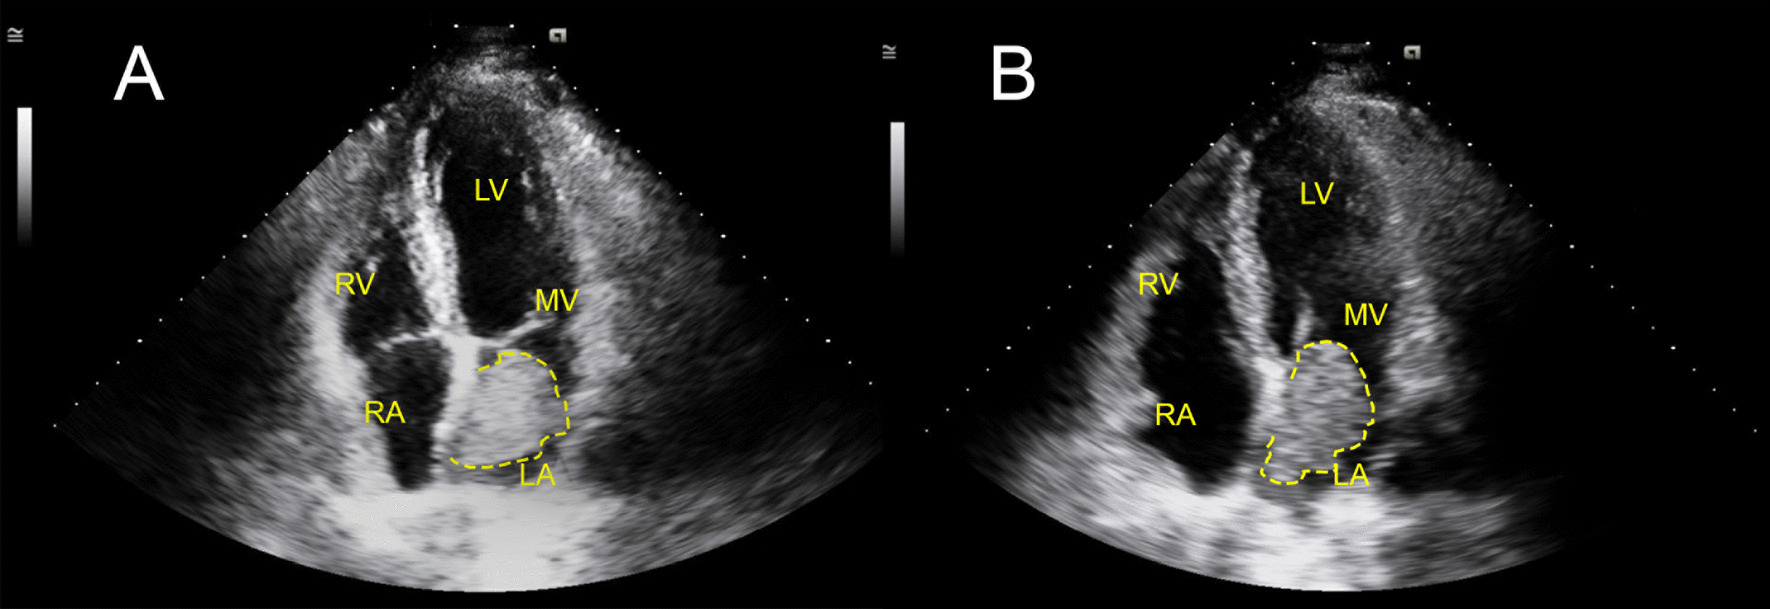

Transthoracic echocardiogram (TTE) showed a Left Ventricular Ejection Fraction (LVEF) of 60–65%, a positive bubble study and a mass in the left atrium estimated to be 3 cm × 4.8 cm, that was observed obstructing the mitral valve during diastole (Fig. 2a, b). The mass was a mobile, hyperechoic structure in the left atrium suggestive of cardiac myxoma or thrombus. Transthoracic echo further characterized the heterogeneous hyperechoic mass, showing hypoechogenic areas representing space neighboring the stalk (Fig. 3a). Definity enhanced contrast imaging of the myxoma similarly showed a heterogeneous mass which is representative of the mass’s vascularity, a characteristic finding which can help differentiate myxomas from thrombi, which tend to have a more homogeneous echogenicity (Fig. 3b).

Fig. 2.

Transthoracic Echocardiogram During Systole and Diastole. a Left atrial myxoma attached to interatrial septum measuring approximately 3 cm × 4.8 cm. b Independently moving myxoma shown obstructing the mitral valve orifice during diastole. LA left atrium; LV left ventricle; RA right atrium; RV right ventricle